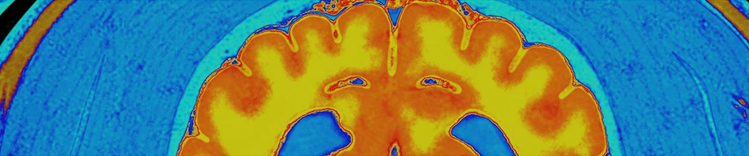

RISONANZA MAGNETICA CEREBRALE

Cambiamenti del cervello durante l'invecchiamento

I cambiamenti fisici del cervello associati all'invecchiamento comprendono:

- Atrofia (restringimento) del tessuto in alcune regioni

- Aumento del volume ventricolare

- Perdita di neuroni e sinapsi e ridotta formazione di nuovi neuroni

- Accumulo di proteine anomale